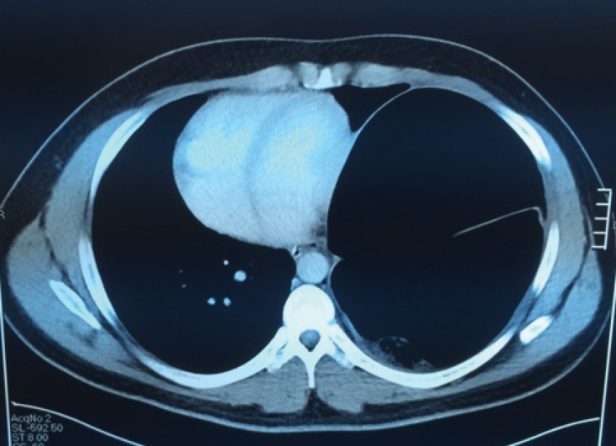

CT θώρακος-τραχήλου. Κόκκινα βέλη — Πολύ μεγάλη οπισθοστερνική βρογχοκήλη. Κίτρινα βέλη — Κλείδες (Ευγενική παραχώρηση Dr. V. Penopoulos)